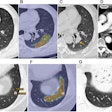

False-negative breast exams on the rise